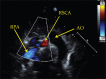

Isolation of the right subclavian artery (RSCA) is rare, and this finding in association with d-transposition of the great arteries (d-TGA) is extremely unusual. We present a case of an isolated RSCA in a newborn with d-TGA in whom the clinical presentation was diagnostic. We discuss the imaging modalities used to confirm the diagnosis, the embryological basis of the finding, and the surgical repair.